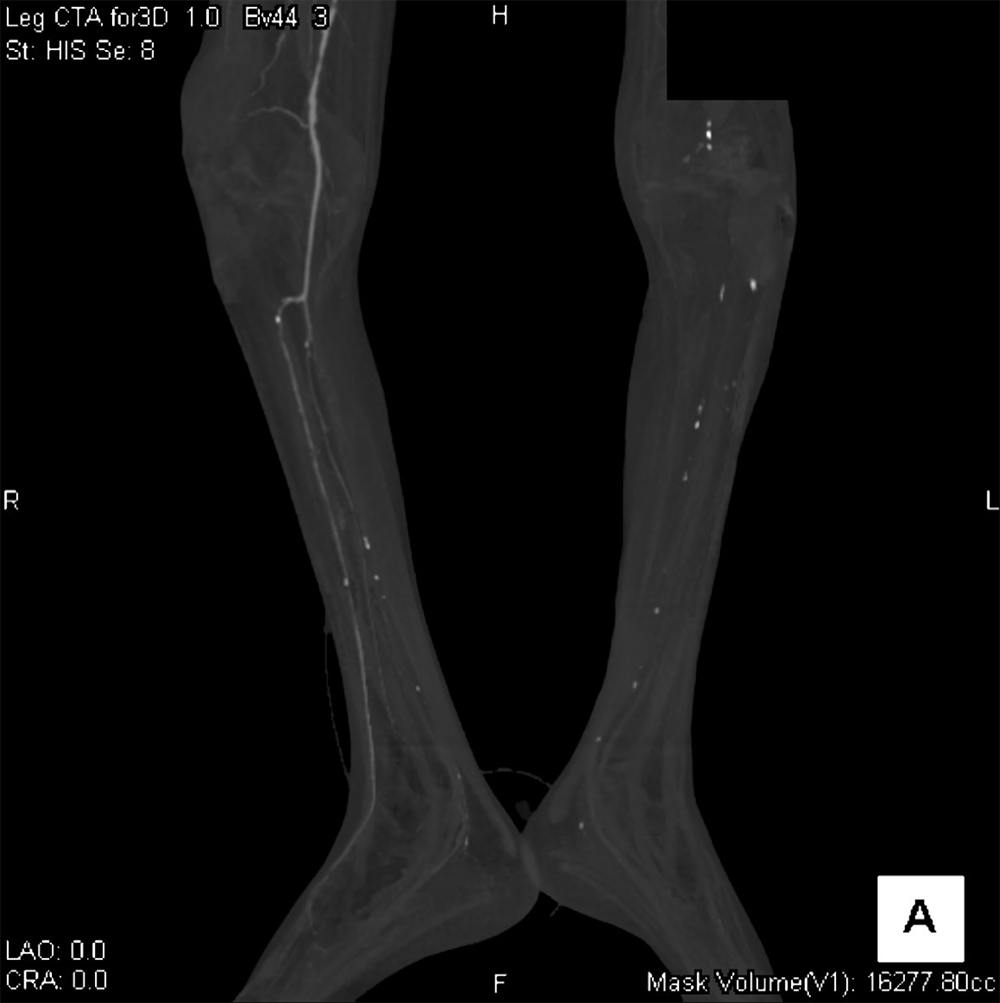

60代男性。高血圧、糖尿病、脂質異常症、喫煙など多数の既往がある。他院にて進行する下肢壊疽を認め、切断目的に当院に転院。入院1日目に下肢造影ダイナミックCTが施行された。動脈相で両側浅大腿動脈近位に閉塞を認めた。右下肢では側副路を介して膝窩~下腿三枝の細い描出が確認されたが、左下腿三枝の描出は認められなかった。左下腿の軟部組織は腫脹し、対側にくらべ造影効果の減弱と多量のガス像も見られたことから左優位の閉塞性動脈硬化症に伴う左下腿壊疽と診断した。感染コントロール困難で入院2日目に急変し死亡した。

当該疾患の診断における造影CTの役割

下肢造影CTを撮像すると下肢動脈の狭窄形態や病変前後の血管走行、石灰化やプラークなど血管壁の性状評価、側副血行路の評価、多発病変の有無、その他に潰瘍病変、動脈瘤、解離の有無など非常に多くの情報を得ることができる。症例によっては遅延相を追加することで静脈の走行や位置関係の他、静脈内血栓の評価も行うことができる。さらに多断面再構成像や3次元像を構築することで血管の状態をイメージしやすくなり、その後の治療においてはカテーテルによる血行再建術のリファレンスとして使用するなど治療にも大変有用な検査と考えられる。治療後においては効果判定や合併症の有無、その後の経過観察に有用である。

CT技術や撮像プロトコル設定について